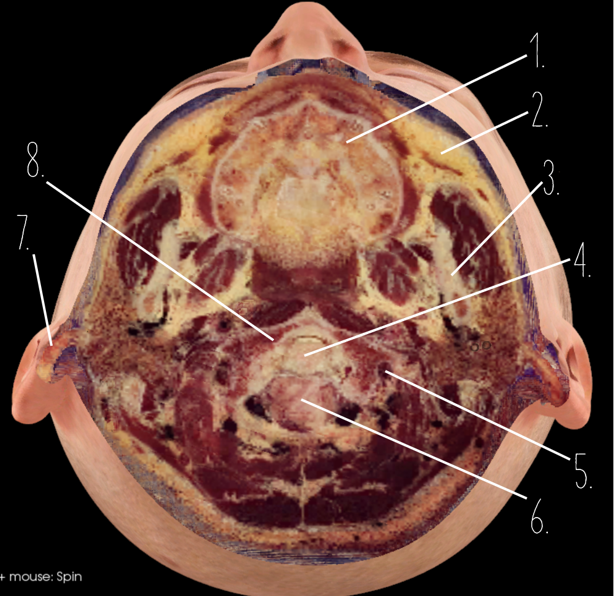

1?

Nasal Bone

2?

Maxillary Sinus

3?

External Acoustic Meatus

4?

Pons

5?

Cerebellum

6?

Mastoid Air Cells

7?

Mandibular Condyles

8?

Sphenoid Bone

9?

Maxillary Bone